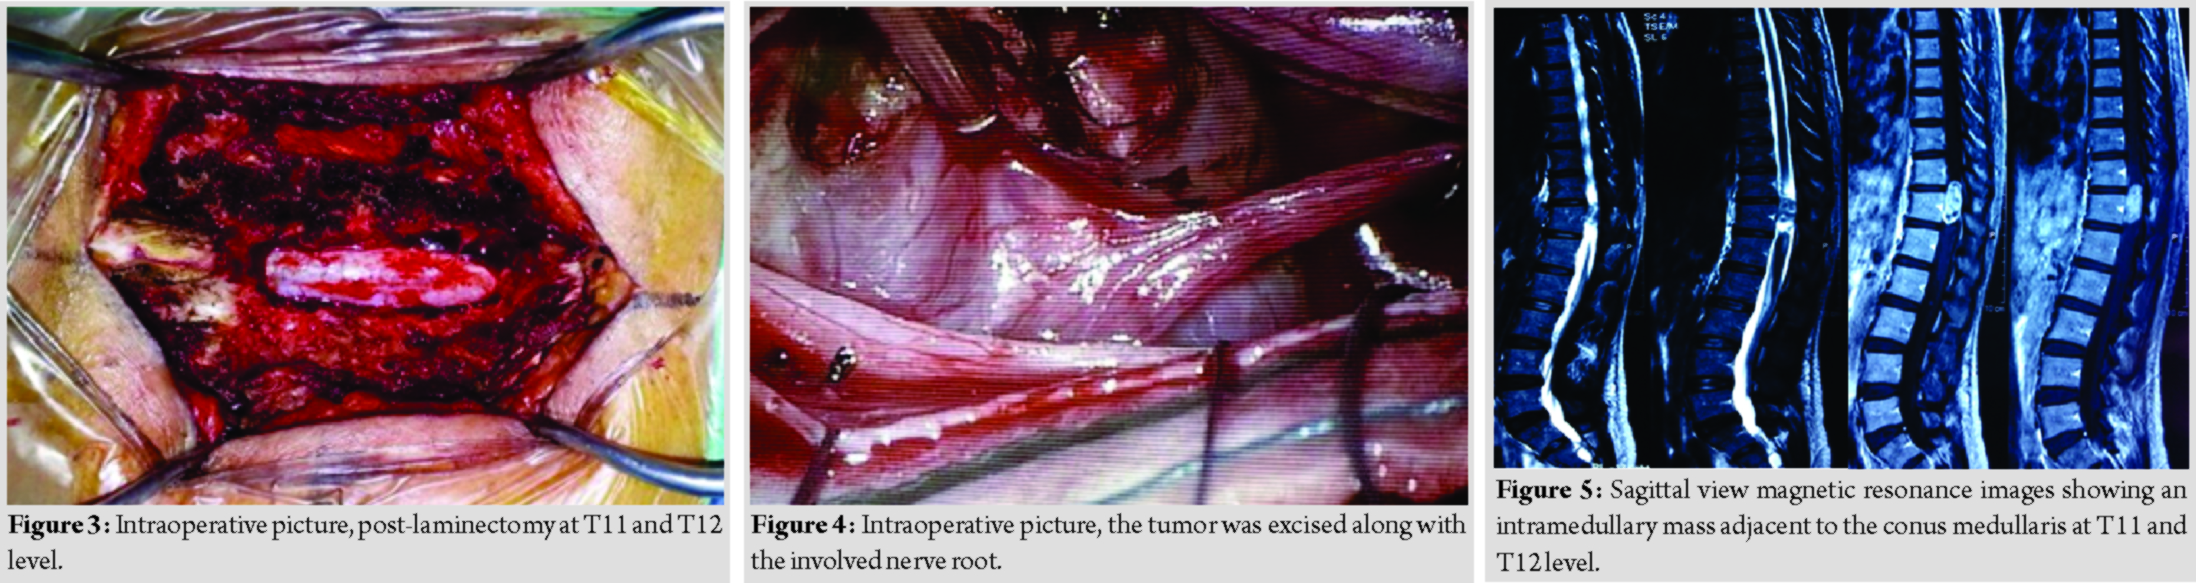

She underwent laminectomy of T11 and T12 with microscopic assisted excision of the tumor. The mass was located intradural extramedullary and was successfully removed completely; however, the nerve root had to be sacrificed (Fig. 3 and 4).

Case 2

A 44-year-old lady presented with back pain and bilateral lower limb weakness for 2 years duration. She then progressed to develop urinary incontinence for 2 months duration. Clinical examination reveals bilateral lower limb hypertonia, lower limb power was Grade 0, and reflexes were brisk, sensory reduced from T11 dermatome onward. Magnetic resonance imaging reveals an intramedullary mass adjacent to the conus medullary (Fig. 5 and 6). Differential diagnosis at that point of time was astrocytoma and ependymoma. She underwent laminectomy of T11 and T12 with microscopic assisted tumor excision (Fig. 7 and 8). The mass was removed completely without having to sacrifice the involved nerve root. At 1-week post-operative, she was able to ambulate with aid. At 1-month post-operative, she was able to ambulate without aid, regained her bladder control and back pain resolved. Final histopathological findings reveal schwannoma.